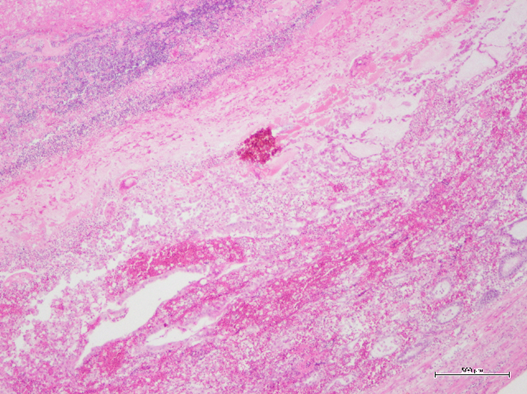

出血性腸炎の組織像(弱拡大、HE染色_ヘマトキシリン・エオジン染色)

(ヘマトキシリンとエオジンという2つの染料を用いて組織や細胞を染色する技術)

■死因として一番多くみられた出血性腸炎では、特に小腸後部の漿膜面(漿膜面_体腔内の臓器を包む最も外側の膜)、内腔が暗赤色を示し、組織学的には出血性腸炎の典型として認められました